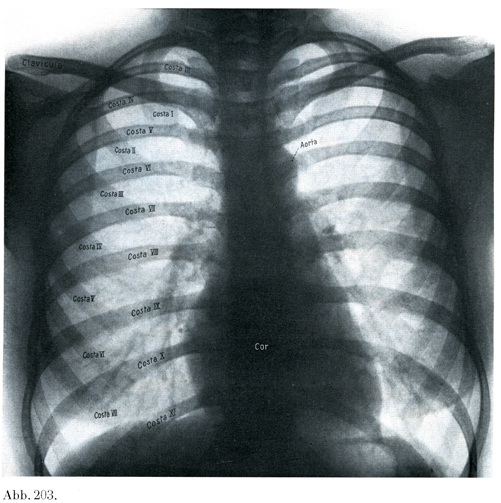

[図203]20才の少女の胸郭のレントゲン像 背腹照射(5/12)